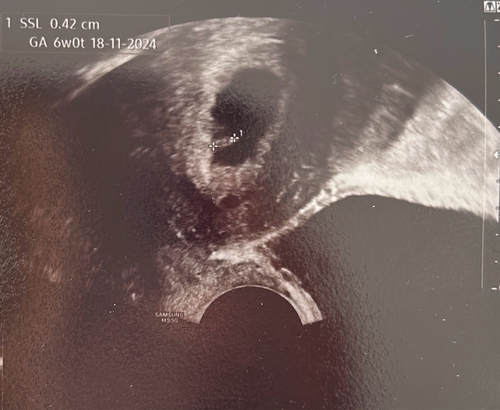

Bin sehr gespannt ob man das Herzchen schon schlagen sieht💕

Ich darf Freitag zum ersten US in unsere KiWu Klinik. Dann bin ich 6+3.

Ich war gestern bei 6+4 und da konnte man das Herzchen tatsächlich schon schlagen sehen 💖

Ich hab nächste Mittwoch den ersten Termin, bei 6+3, bin schon soooo gespannt, ob man das Herzchen sieht!

Ich hab einen Kringel im Kringel gesehen 😊 Dottersack und Embryonalgewebe. Meine FÄ glaubt aber, dass sie mich nochmal um paar Tage zurück datieren muss, aber das macht sie erst dann, wenn man mehr erkennen kann. Fürs erste bin ich glücklich und beruhigt 💕

Mein erster Termin lief super. Ich bin erleichtert und sehr glücklich. Bin jetzt 6+0, man hat das Herz flimmern gesehen und habe direkt meinen Mutterpass bekommen.